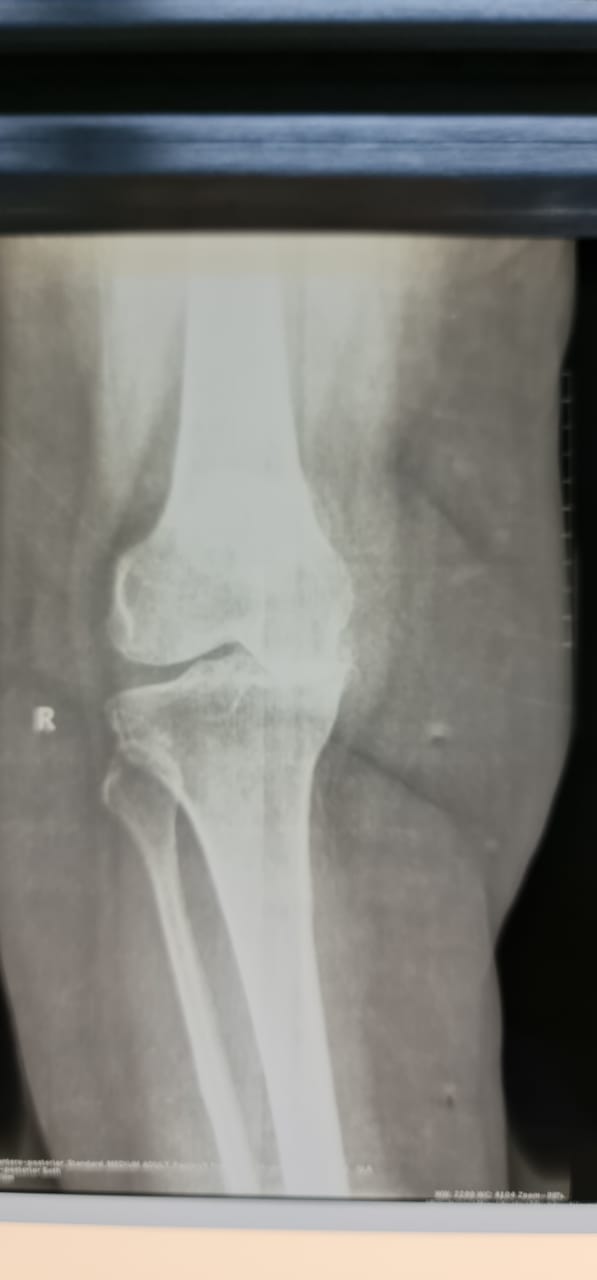

نجح فريق طبي بمستشفى حريملاء العام في إنهاء معاناة مريضة سعودية عمرها ٦٤ سنة تعاني من احتكاك شديد وخشونة بالركبة اليمنى من الدرجة الرابعة .

وأوضحت “صحة الرياض” ، أن المريضة كانت تعاني أيضاً من تآكل كامل بالغضاريف وإنحراف داخلي بالساق ، وصعوبة بالمشي والحركة.